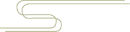

X 线检查无特殊意义,以 MRI 检查最为敏感,关节周围软组织可见不同程度水肿,肩峰下可见积液,以及大量直径不等(1 ~ 10 mm)的类圆形占位,与周围肌肉组织相比呈等 T1 稍长 T2 信号。

无明显症状的关节病,米粒体滑囊炎会被忽略漏诊。主要需与色素沉着绒毛结节性滑膜炎 (PVNS) 和滑膜软骨瘤相鉴别。鉴别诊断要点主要以 MRI 为主。

化生软骨往往呈叶状,未钙化时的 T1 像为等信号,T2 加权像为高信号;已经钙化的则 T1 和 T2 加权像均为高信号。